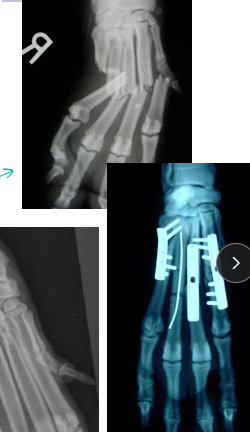

Carpal, Metacarpal, Digital, Metatarsal Fractures

Very common, greyhounds

Carpal: lag screw

Metacarpal and Metatarsal: medical tx most common

Tx: closed reduction + caudal splint (Rx #1), IM pins/plates + caudal splint (Sx)

Sx indicated if open, grossly displaced, intra-articular, or all 4 fractured

Digital: caudal splint bandage for 6w